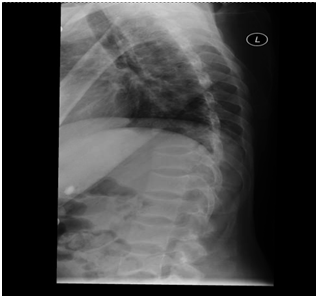

A skeletal survery performed during the hospital stay showed findings consistent with osteomalacia including arrest lines (distal femur and proximal tibia in Figure 3), looser’s zones (shaft of femur in Figure 4), frontal bossing (Figure 5) and multiple endplate compression deformities in the thoraco-lumbar spine (Figure 6).

Figure 6 X-Ray of Thoracolumbar spine showing “Fish Vertebrae” suggestive of compression fractures.